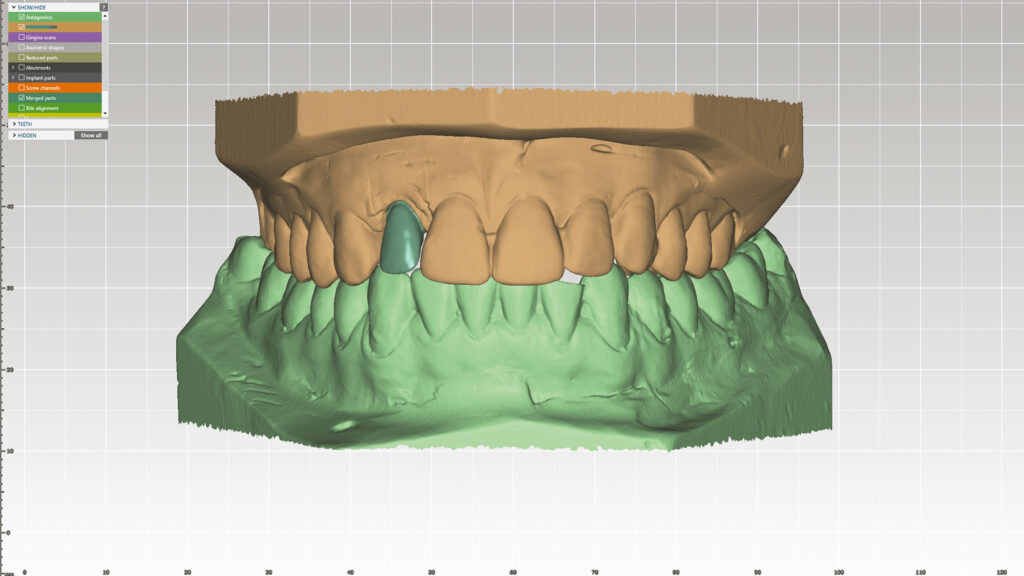

Digitales Set-up (DTX Studio)

Nachdem Zahn 12 auf dem gedruckten Modell entfernt worden ist, kann das Modell mit dem Laborscanner (KaVo LS3) digitalisiert und ein Design-Setup am Bildschirm konstruiert werden (Abb. 8). Die Software-Bibliothek bietet eine breite Auswahl an Zähne in verschiedenen Formen sowie Größen und erlaubt eine Zahnaufstellung in optimaler Position (Abb. 9 und 10). Diese Vorgehensweise spart Zeit und ermöglicht noch mehr ästhetische Kreativität. Der KaVo LS3-Desktop-Scanner ist für die Planung von Implantatversorgungen mit DTX Studio verbunden. DTX Studio ist eine digitale Plattform, die Diagnose und Behandlung verbindet und die Kommunikation im Behandlungsteam optimiert.

On-screen Design

der Restauration

Digital gefertigte ASC-Implantatrestaurationen sind bei uns zum Standard geworden und bieten die Freiheit, Position und Angulation individuell zu gestalten. Sowohl das Emergenzprofil als auch die Kronenposition der Restauration können individuell gestaltet werden. Vorteil von DTX Studio Lab (Nobel Biocare) ist, dass durch die digitale Fertigung und die besondere Art des Scannens eine verschraubbare Zirkonoxid-Implantatkrone in idealer Form auf Basis einer vorhersagbaren Platzierung gestaltet werden kann (Abb. 48). Mit dem ASC-System kann der Schraubenzugang für maximale Stabilität auf der palatinalen Seite platziert werden (Abb. 49). Abbildung 50 zeigt das OnScreen-Design der verschraubbaren Implantatkrone mit einem Angulationswinkel von 23° und die Gestaltung der labialen Fläche, die später mit Keramik verblendet wird (Abb. 51). Dieser letzte, wichtige Arbeitsschritt, der Weg zur individuellen Ästhetik, ist und bleibt vorerst analog. So lässt sich zusammenfassen, dass wir in unserem Labor „DIGILOG” arbeiten, eine Kombination aus zwei Welten, konservativ und zukunftsorientiert. Zwei Welten, die sich gut verbinden lassen – digital und analog.